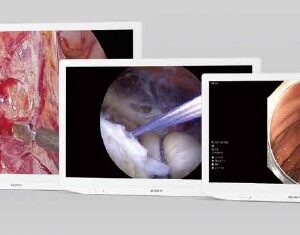

SKU: n/a - Sistemas de Grabación, Sony

Grabador Digital – HVO-4000MT

El HVO-4000MT es un grabador de vídeo 4K, 3D y 2D para uso médico diseñado para grabar vídeos e imágenes en 4K de sistemas de cámaras endoscópicas y laparoscópicas, microscopios quirúrgicos y otros sistemas de captación de imágenes compatibles.

SKU: n/a - Monitores Médicos, Monitores Sony

Monitor Medico – LMD-2110MD

El monitor LMD-2110MD incluye un panel LCD de 21,5″ con resolución Full HD (1920 x 1080) y procesamiento de señal de 10 bits. De conformidad con las normas de seguridad médica y los estándares EMC, el monitor proporciona una imagen nítida y precisa en alta definición.

SKU: n/a - Monitores Médicos, Monitores Sony

Monitor Medico – LMD-2435MD

El LMD-2435MD muestra imágenes y vídeos en 2D procedentes de cámaras endoscópicas, laparoscópicas y otros sistemas de escáner médicos compatibles. Se ha mejorado su funcionamiento flexible con una selección de modos de imagen, mientras que una interfaz de usuario intuitiva asiste al usuario con tan solo pulsar unas teclas. Diseñado para su integración en los entornos quirúrgicos actuales, el monitor se puede instalar cómodamente en el techo o integrarse en un carrito médico moderno. Las interfaces analógicas y digitales simplifican la conexión con una amplia gama de fuentes de imagen de HD y Definición Estándar.

SKU: n/a - Monitores Médicos, Monitores Sony

Monitor Medico – LMD-2735MD

El LMD-2735MD muestra imágenes y vídeos en 2D procedentes de cámaras endoscópicas, laparoscópicas y otros sistemas de escáner médicos compatibles. Se ha mejorado su funcionamiento flexible con una selección de modos de imagen, mientras que una interfaz de usuario intuitiva asiste al usuario con tan solo pulsar unas teclas. Diseñado para su integración en los entornos quirúrgicos actuales, el monitor se puede instalar cómodamente en el techo o integrarse en un carrito médico moderno. Las interfaces analógicas y digitales simplifican la conexión con una amplia gama de fuentes de imagen de HD y Definición Estándar.